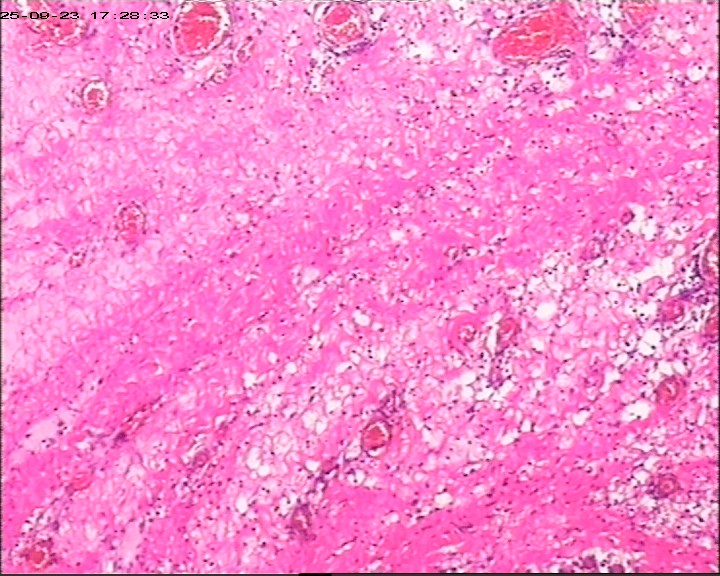

肛周脓肿组织,请帮忙看看,谢谢

肛周出血肿块伴疼痛,红肿6天。脓肿切开引流术+内痔结扎术

臀部皮肤病损

灰白灰红带皮组织3块,大小为3*2*0.5cm

鳞状上皮增生伴湿疣样改变

生炎+出血。

急、慢性炎,伴出血。